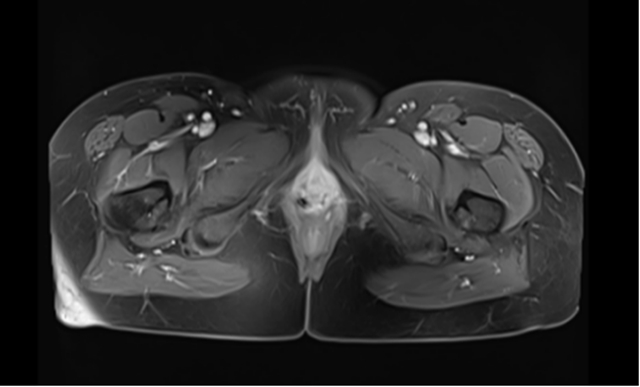

随后的近距离放疗(后装),以及两周期的“替雷利珠单抗注射液+TP”方案化疗,还有长达两年的“替雷利珠单抗注射液”维持治疗,在医护团队的精心照料下,赵女士的病情持续好转。期间复查影像学显示,肿瘤没有复发进展,曾经困扰她的外阴瘙痒、肿胀、疼痛也明显好转。